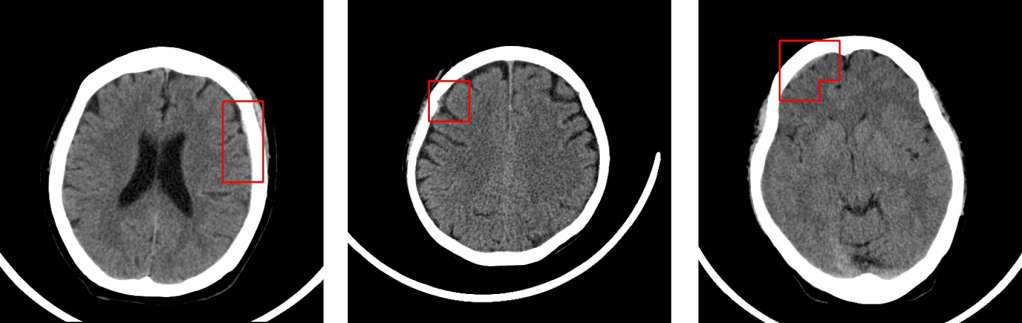

Deep01, a Taiwanese startup that develops software to help doctors interpret CT brain scans more quickly, announced today that it has raised $2.7 million. The funding was led by PC maker ASUSTek.

Created for use by emergency departments, Deep01 says its software can detect acute intracerebral hemorrhage with an accuracy rate of 93% to 95%, within 30 seconds.